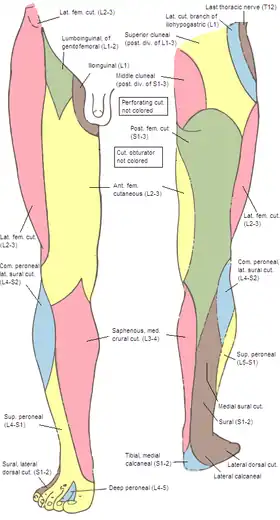

Cutaneous nerves of the right lower extremity. Front and posterior views. (Posterior div of sacral visible in pink at upper left.) | |

The medial clunial nerves innervate the skin of the buttocks closest to the midline of the body. Those nerves arise from the posterior rami of sacral spinal nerves (S1, S2, and S3).